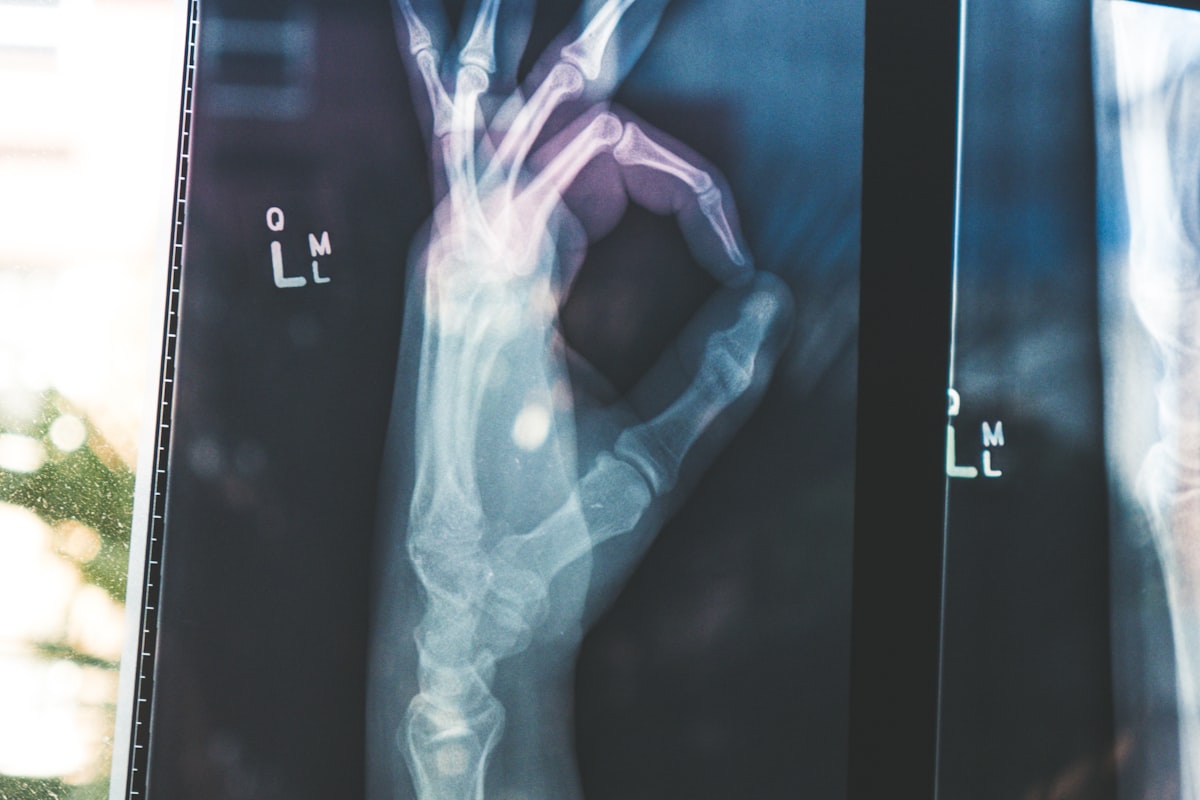

- 西洋医学的評価: 画像検査(X線、MRIなど)の結果や血液検査データも参考にし、総合的な治療計画を立案する。